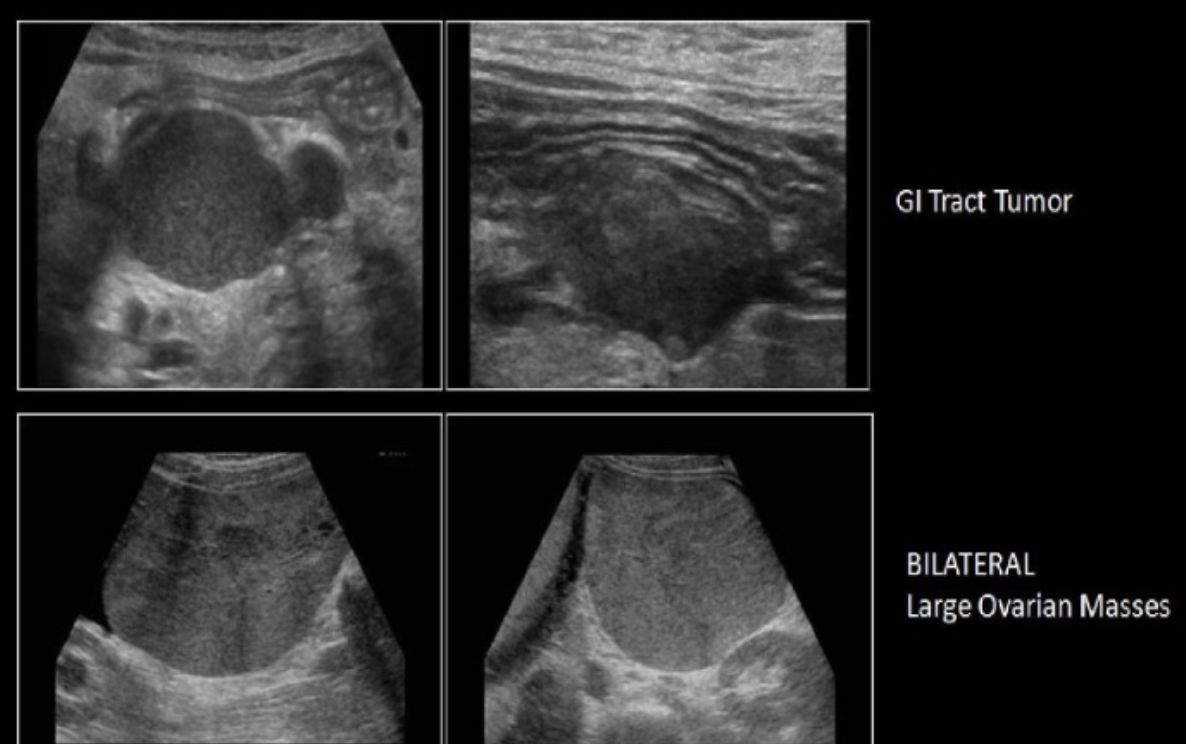

formation of bilateral solid ovarian neoplasm is high suspicious for

a) yolk sac tumor

b) serous cystadenoma

c) Krukenberg tumor

d) dysgerminoma